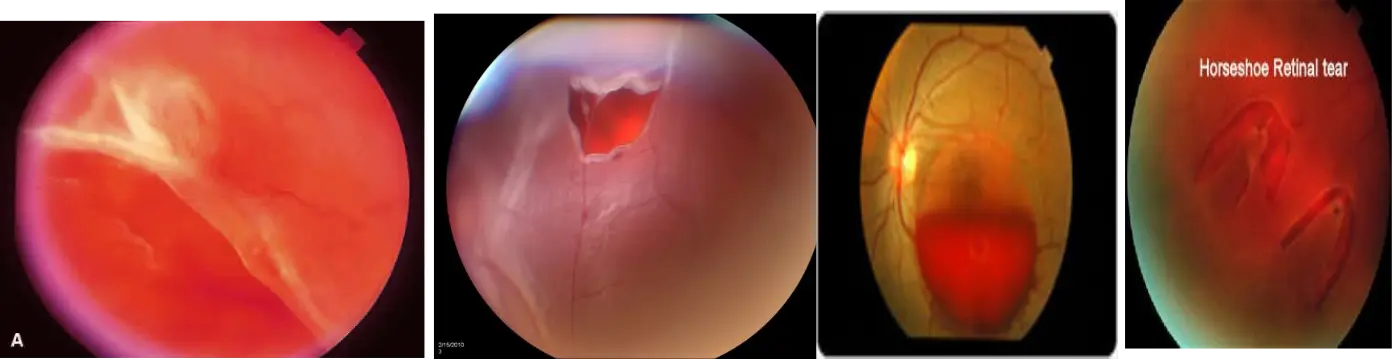

Retinal Detachment

Common presentation: Sudden, painless vision loss

Treatment:

- Close the tears: by photocoagulation, condensation, electric coagulation

- If total: Surgery:, Scleral buckling: Virectomy and Retinopexy

Central retinal vein occlusion

all of the following are a complication of this case EXCEPT ?

- A) ischemia

- B) Macular edema

- C) Neovascular glaucoma

- D) cataract

Wet macular age related degeneration